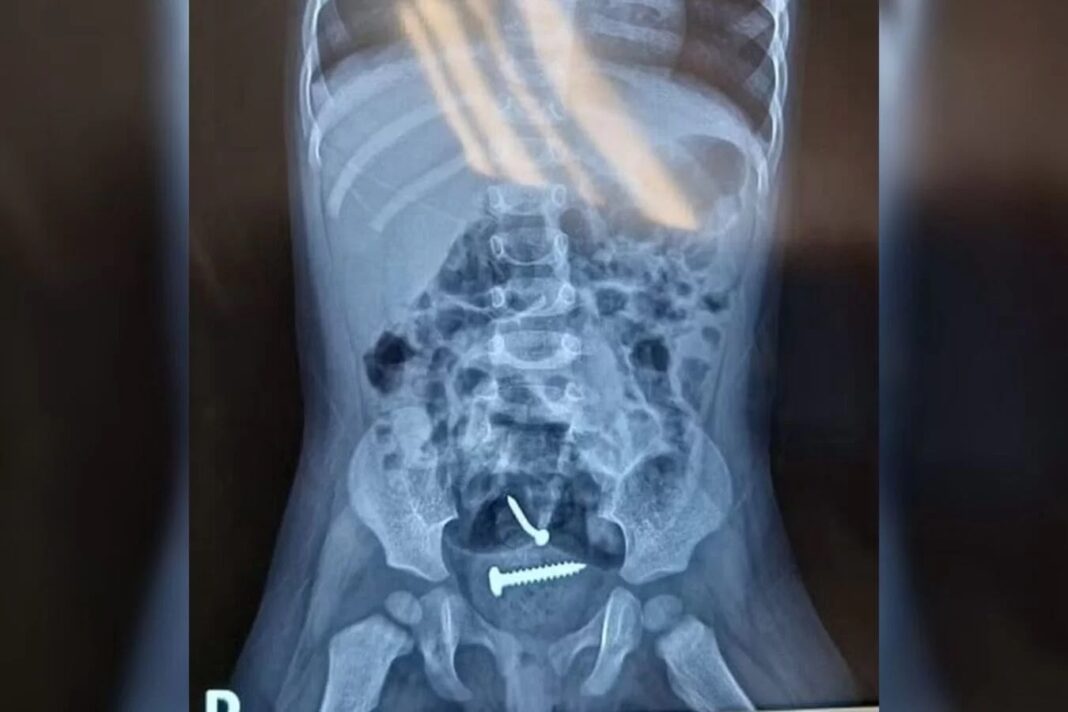

A soldada Gisele Alves Santana, encontrada morta com um tiro...